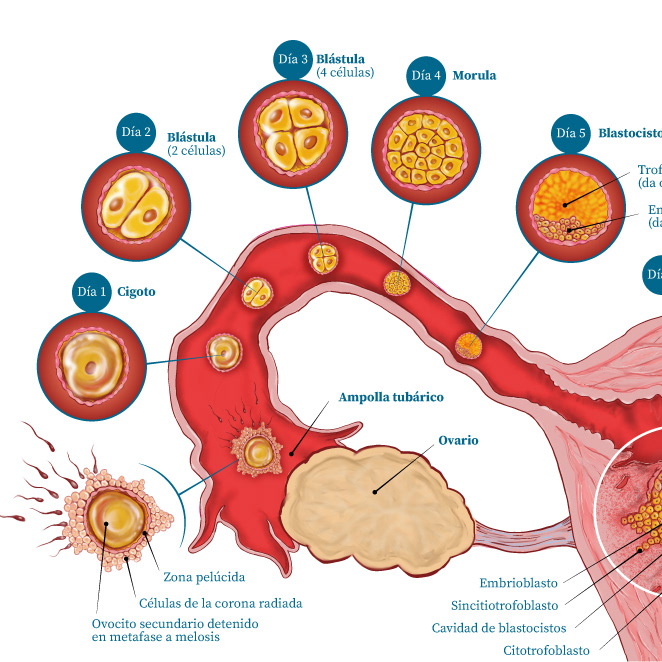

Infografía / Ginecología